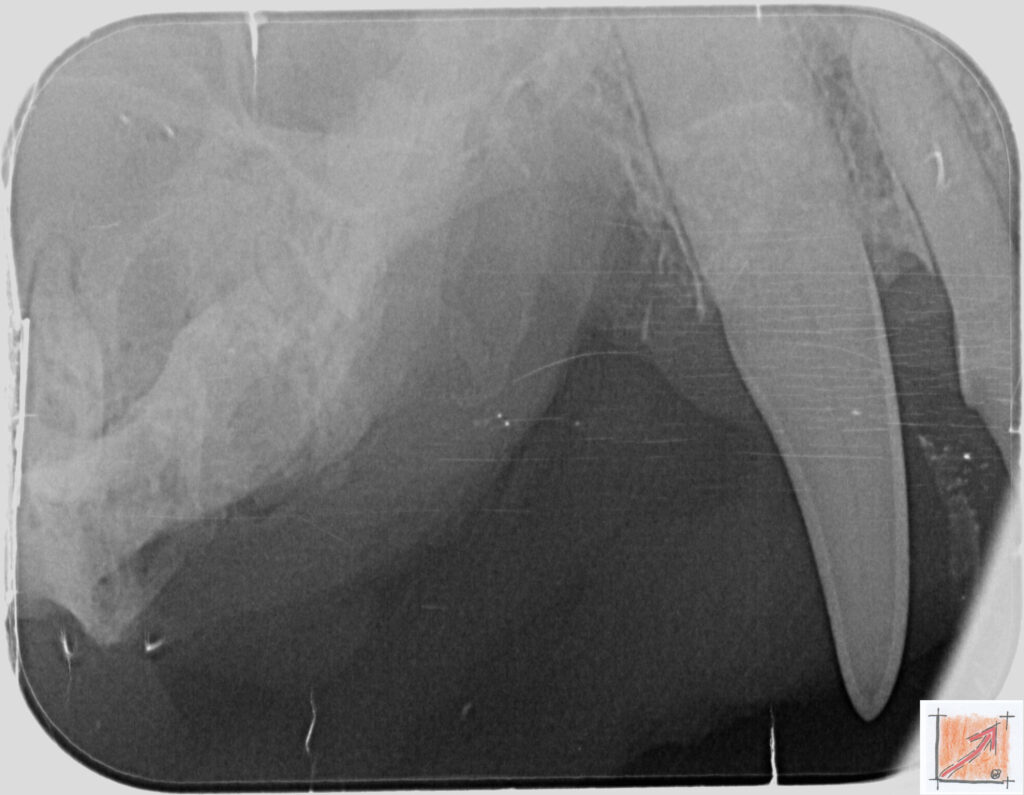

Röntgenbilder vom Thierrischen Orakel bei der Zahn-OP:

Warum Dentalröntgen beim Chihuahua lebenswichtig ist:

Ein Blick hinter die Kulissen von Chihuahua-Zähnen:

In dieser Galerie zeigen wir exklusive intraorale Röntgenaufnahmen einer Zahn-Operation beim Thierrischen Orakel als Chihuahua vom BauFachForum. Während oberflächlicher Zahnstein oft sichtbar ist, verbirgt sich die wahre Gefahr für das Herz meist unter dem Zahnfleischsaum.

Das digitale Dentalröntgen ist der Goldstandard in der modernen Tiermedizin, um parodontale Entzündungsherde und Wurzelabszesse sicher zu diagnostizieren. Für Chihuahuas wie dem Thierrischen Orakel, mit Mitralklappeninsuffizienz ist dieser diagnostische Schritt essenziell. Nur wenn versteckte Bakterienherde an der Zahnwurzel oder mit dem Fachbegriff Apikalabszesse erkannt und saniert werden, kann das Risiko einer bakteriellen Endokarditis oder einfach ausgedrückt einer Herzinnenhautentzündung minimiert werden.

Unsere Aufnahmen von Patienten dem Thierrischen Orakel verdeutlichen den Unterschied zwischen einer rein optischen Zahnreinigung und einer medizinisch fundierten Sanierung unter Röntgenkontrolle.

Chihuahua Mitralklappeninsuffizienz Trachealkollaps:

Wichtig ist im Vorfeld die Zahnhygiene des Chihuahuas. Die Bilder zeigen Dentale Röntgenbilder vom Thierrischen Orakel als Chihuahua-Hund während seiner Zahn-OP. Darstellung von Kieferknochen und Zahnwurzeln zur Diagnose von Parodontitis.

Zahnröntgenaufnahme bei Chihuahua Thierry:

Untersuchung der Zahnwurzeln auf Entzündungsherde als Prophylaxe gegen bakterielle Endokarditis.

Intraorales Dentalröntgen eines Chihuahuas:

Die Bilder zeigen Zähne und Wurzelstrukturen im Unterkiefer zur Planung einer Extraktion bei hochgradigem Zahnstein.